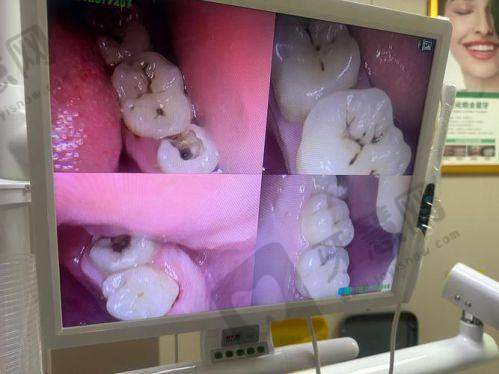

深圳明森数智口腔门诊部成立于2016年11月09日,是明森健康投资旗下企业,是经相关部门批准设立的正规口腔医疗机构。诊疗项目丰富,涵盖镶牙种植牙、牙齿矫正、儿牙、牙周病治疗、牙齿美白、补牙等。特色技术及优势明显,种植牙项目以“技术 + 性价比”双优势著称,提供从韩国进口到瑞士高端的多元化选择。诊疗环境温馨舒适,周边交通便利。引进了进口材料及设备,严格遵循齿科协会的双重高温高压消毒标准。医院规模方面,人员规模少于50人。医生团队实力强大,由众多有三等甲国有医院工作经验的从业多年医生组成。凭借优质的服务和良好的技术,在患者中拥有较高的评价和口碑。

1. 种植牙项目:以“技术 + 性价比”双优势著称,提供从韩国进口到瑞士高端的多元化选择,如韩国登腾种植牙、美国皓圣种植牙、德国贝格种植牙、法国安卓健种植牙等,满足不同患者的需求。

3. 消毒标准严格:严格遵循齿科协会的双重高温高压消毒标准,为患者提供安心、卫生的诊疗环境,有效避免交叉感染。